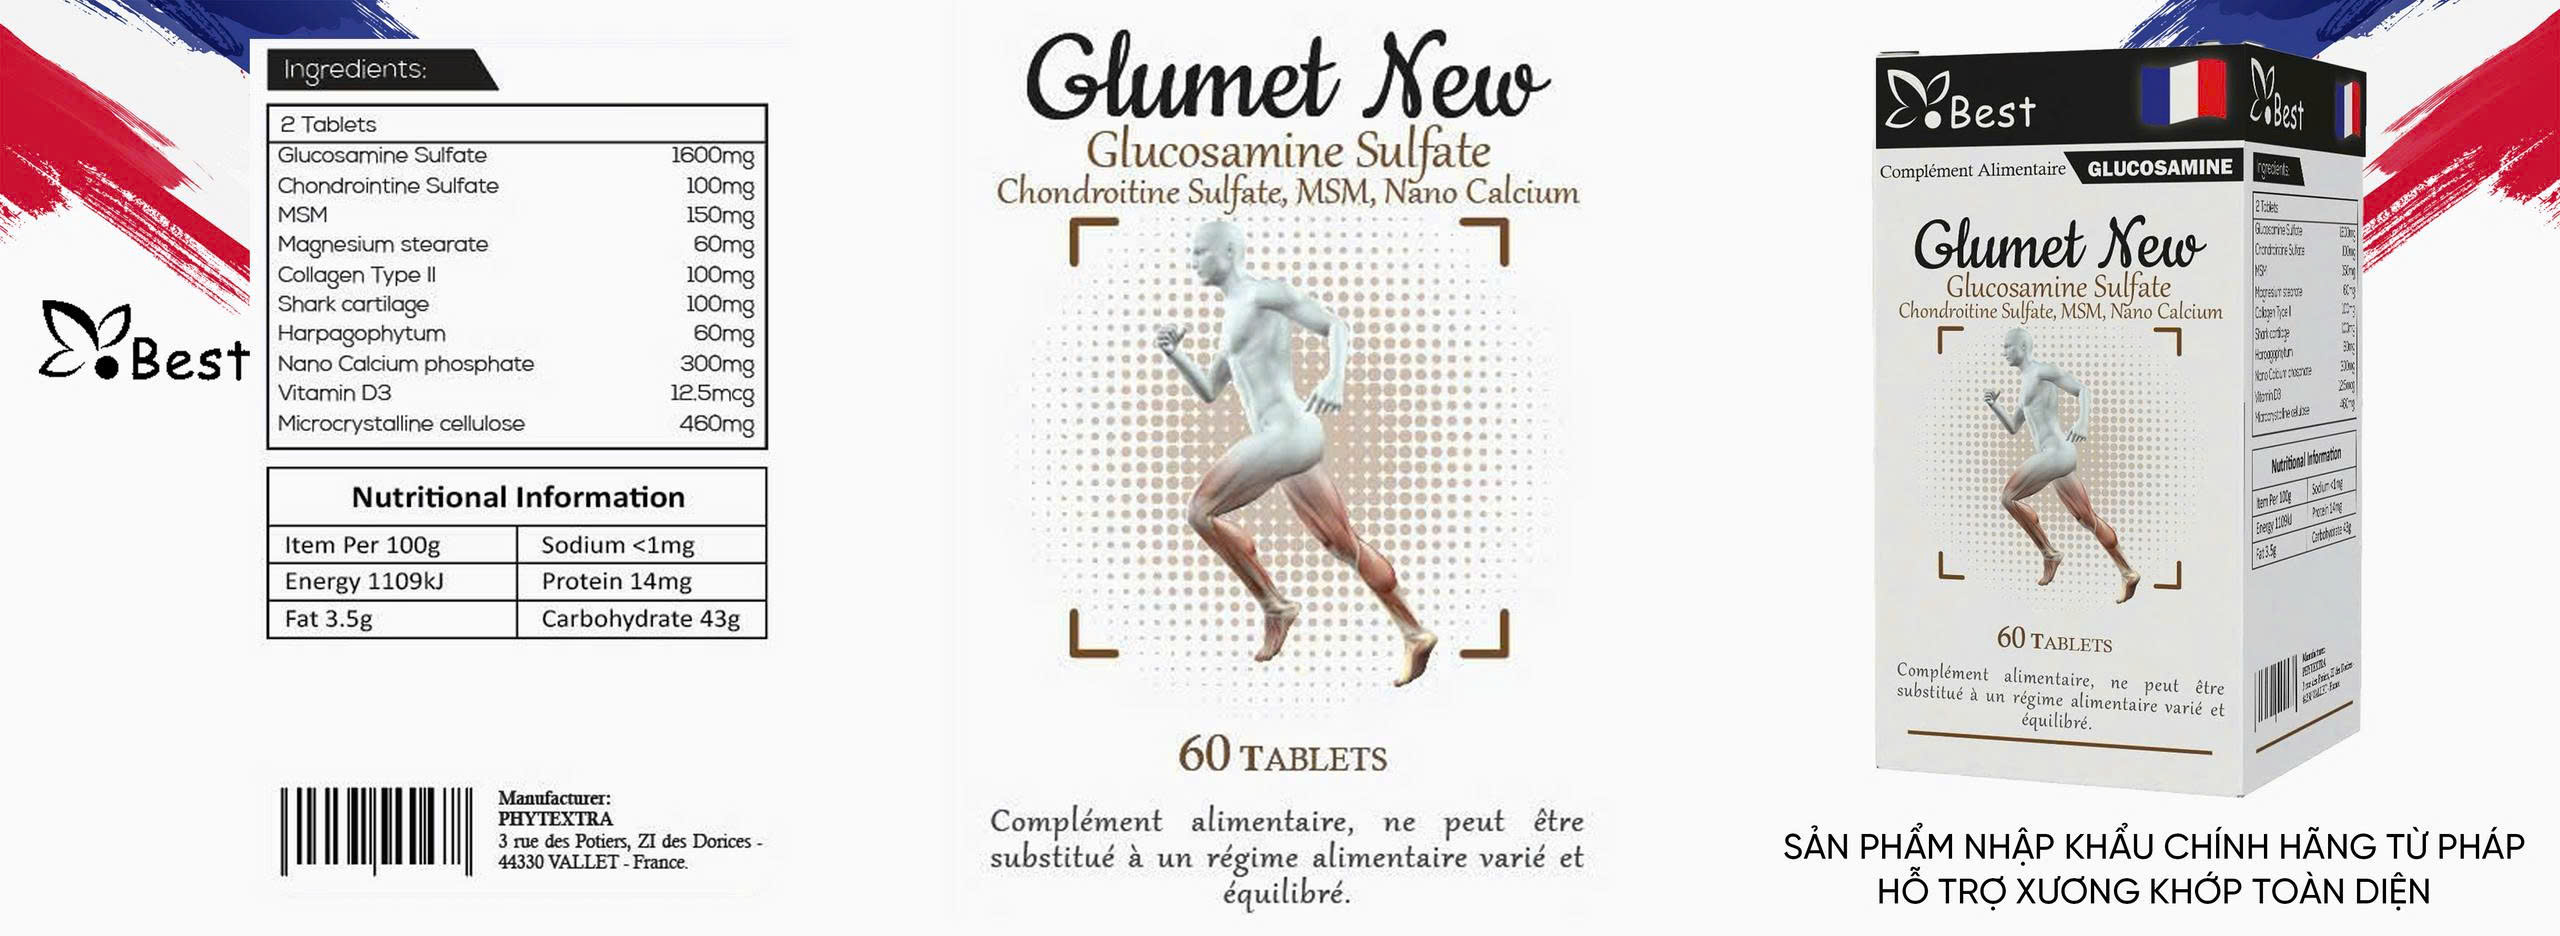

Trên thị trường hiện nay, Glucosamine chủ yếu tồn tại dưới hai dạng chính là Glucosamine Sulfate và Glucosamine Hydrochloride (HCl). Mặc dù cả hai đều có tác dụng hỗ trợ khớp, nhưng các nghiên cứu lâm sàng quy mô lớn trên thế giới thường ưu tiên sử dụng dạng Sulfate nhờ khả năng hấp thụ và giữ lại trong các mô sụn tốt hơn. Glucosamine Sulfate cung cấp thêm gốc lưu huỳnh (Sulfur) – một nguyên tố cực kỳ quan trọng giúp cơ thể tổng hợp nên các sợi Collagen và Proteoglycan, vốn là hai thành phần chính tạo nên độ dẻo dai cho sụn khớp.

Trong khi nhiều dòng sản phẩm thông thường sử dụng dạng HCl để giảm giá thành sản xuất, Glumet New lại kiên định với dạng Glucosamine Sulfate. Sự khác biệt này giúp sản phẩm không chỉ dừng lại ở việc bổ sung dưỡng chất mà còn thực sự tham gia vào quá trình tái tạo lại những mảng sụn đã bị bào mòn. Việc chọn đúng dạng Sulfate chính là bước đầu tiên để đảm bảo quá trình giảm đau xương khớp an toàn, tránh tình trạng nạp vào cơ thể những hoạt chất khó hấp thụ, gây áp lực lên hệ tiêu hóa và bài tiết mà không mang lại hiệu quả trị liệu thực sự.

Một yếu tố then chốt khác tạo nên sự khác biệt của Glumet New chính là hàm lượng hoạt chất. Đa số các dòng Glucosamine thông thường trên thị trường chỉ cung cấp mức hàm lượng từ 500mg đến 1000mg trong một liều dùng. Theo các chuyên gia xương khớp tại Pháp, đây là mức hàm lượng “duy trì”, chưa đủ để kích thích mạnh mẽ quá trình tái tạo mô sụn đối với những người đã bước vào giai đoạn thoái hóa hoặc thường xuyên bị đau nhức. Ngưỡng hàm lượng 1600mg (tương đương với 2 viên Glumet New mỗi ngày) được coi là “ngưỡng hiệu quả” để cơ thể bắt đầu quá trình sửa chữa các vi tổn thương tại ổ khớp.

Khi cơ thể nhận đủ 1600mg Glucosamine Sulfate mỗi ngày, quá trình tổng hợp dịch khớp sẽ diễn ra mạnh mẽ hơn, giúp làm trơn các đầu xương và giảm thiểu ma sát mỗi khi vận động. Đây là bí quyết giúp người dùng Glumet New cảm thấy sự thay đổi rõ rệt ở các khớp gối, cổ tay hay cột sống chỉ sau một thời gian ngắn sử dụng. Việc nạp đủ hàm lượng cần thiết không chỉ giúp giảm đau xương khớp nhanh chóng mà còn ngăn chặn sự tiến triển của bệnh, giúp người trung niên và cao tuổi duy trì được khả năng vận động linh hoạt mà không cần đến sự can thiệp của các loại thuốc giảm đau liều cao.

Sự khác biệt vượt trội của Glumet New so với các dòng Glucosamine thông thường còn nằm ở công thức phối hợp đa tầng. Glucosamine đơn thuần chỉ đóng vai trò là “gạch xây” tái tạo sụn, nhưng để giảm các cơn đau viêm cấp tính một cách tự nhiên, cơ thể cần thêm các chất kháng viêm lành tính. Glumet New đã tích hợp chiết xuất cây móng quỷ (Harpagophytum) – một dược liệu quý từ châu Âu có khả năng ức chế các tác nhân gây viêm mạnh mẽ. Sự xuất hiện của cây móng quỷ giúp người bệnh giảm đau xương khớp an toàn mà không lo ngại các tác dụng phụ gây loét dạ dày như khi dùng thuốc tây.

Bên cạnh đó, MSM (Methylsulfonylmethane) và Chondroitin có trong sản phẩm đóng vai trò là chất bôi trơn và bảo vệ mô liên kết. Sự phối hợp giữa hàm lượng Glucosamine Sulfate 1600mg và các dưỡng chất thảo dược này tạo ra một “vòng tròn bảo vệ” khép kín. Trong khi Glucosamine tái tạo cấu trúc, cây móng quỷ xoa dịu cơn đau, thì MSM giúp tăng tính linh hoạt của các dây chằng quanh khớp. Điều này tạo nên sự khác biệt hoàn toàn so với việc chỉ uống Glucosamine đơn lẻ, vốn thường chỉ mang lại tác động một chiều và chậm phát huy hiệu quả.

Công nghệ Nano Canxi và tiêu chuẩn chất lượng khắt khe từ Pháp

Khác với nhiều dòng sản phẩm hỗ trợ xương khớp thông thường chỉ tập trung vào phần sụn, Glumet New còn chú trọng đến việc củng cố phần xương dưới sụn thông qua công nghệ Nano Canxi. Các phân tử Canxi kích thước siêu nhỏ kết hợp với Vitamin D3 giúp tăng mật độ xương, tạo ra một bệ đỡ vững chắc cho khớp. Nhiều dòng Glucosamine trên thị trường thường bỏ qua yếu tố xương, khiến người dùng dù khớp đã bớt đau nhưng xương vẫn giòn và dễ tổn thương. Việc tích hợp Nano Canxi thân thiện với dạ dày giúp Glumet New trở thành giải pháp chăm sóc hệ vận động toàn diện nhất hiện nay.

Hơn thế nữa, nguồn gốc nhập khẩu từ Pháp chính là “tem bảo chứng” cho sự khác biệt của Glumet New. Sản phẩm đáp ứng hàng loạt các chứng nhận quốc tế danh giá như GMP, HACCP, ISO 14001:2015 và ISO 9001:2015. Mọi khâu sản xuất từ việc lựa chọn nguyên liệu Glucosamine Sulfate tinh khiết đến quy trình đóng gói đều được kiểm soát nghiêm ngặt. Sự minh bạch về nguồn gốc và các chứng chỉ chất lượng này giúp người dùng hoàn toàn yên tâm khi tìm kiếm một phương pháp giảm đau xương khớp an toàn, tránh xa những sản phẩm trôi nổi không rõ hàm lượng và thành phần trên thị trường.